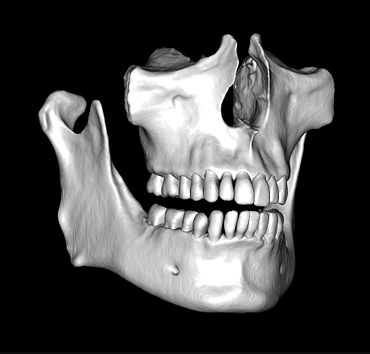

CBCT segmentation

This is one feature that actually made Diagnocat very popular early on. It was the only software that made CBCT segmentation easy. Nowadays, there are several different companies and software that carry out segmentation. Diagnocat was the first and is still arguably the best at it.

So what is Segmentation? It basically means taking the CBCT and delineating all the different 3D structures, bones, individual teeth, etc.

These can then be individually exported via the software by generating STL files from CBCT dicom data. This can be used in other dental software. Jaw STLs can be used in Modjaw (jaw motion capture) for TMJ analysis, for example. As well as in exocad to help visualize the jaws for surgical planning or guide creation.

Being able to take a DICOM file and turn it into STLs is useful for a host of different CAD/CAM indications.

- CBCT segmentation

STLs of upper and lower jaws imported into Modjaw for TMJ analysis in jaw motion. this is made possible by CBCT segmentation using Diagnocat.

The surgical crown lengthening guide was made with the aid of maxilla STL to visualize crestal bone level. Again thanks to CBCT segmentation by Diagnocat.

CBCT Segmentation into STL

Generate STL files from CBCT DICOM data.

Generate maxilla and mandible in one STL file or face, teeth, maxilla, mandible, airway, cranial base, canals as separate STL files.